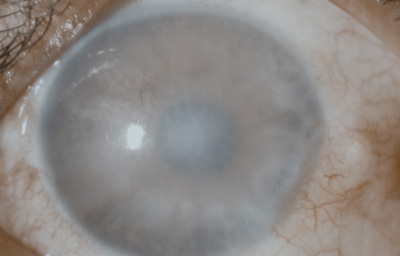

Caso No18.

Paciente masculino de 34 años, agricultor; 20 meses antes de la consulta sufrió picadura en el Ojo Derecho de avispa amarilla “la llaman vaquera” en Saravena. Operado con ltrante a los 4 meses.- Se aplica Optimol

Al examen OD Leucoma denso central con grandes bullas y vaso estromal profundo que penetra a las 6; notable engrosamiento corneal, ( Fistula interna en córnea?) y no panus vascular periférico, midriasis paralítica, goniosinequia en 360o ?.- catarata intumescente, cicatriz quirúrgica superior, Tono digital medio (Foto No 19)

Foto 19 - Leucoma denso con bullas y vaso estromal profundo a las 6

Conducta: Se realiza Queratoplastia penetrante 8.2 mm + Sinequiotomía angular con Viscoelástico + Extracapsular +LIO en OD. En el postoperatorio, injerto trasparente con hipertensión ocular controlada con medicación, gran excavación del Nervio Optico

A los 151 dias de postoperatorio, se aprecia edema del injerto.- Se inició tratamiento; a los 9 meses de postoperatorio se retiraron las suturas, manteniendo el tto antihipertensivo.- EL PACIENTE NO REGRESO